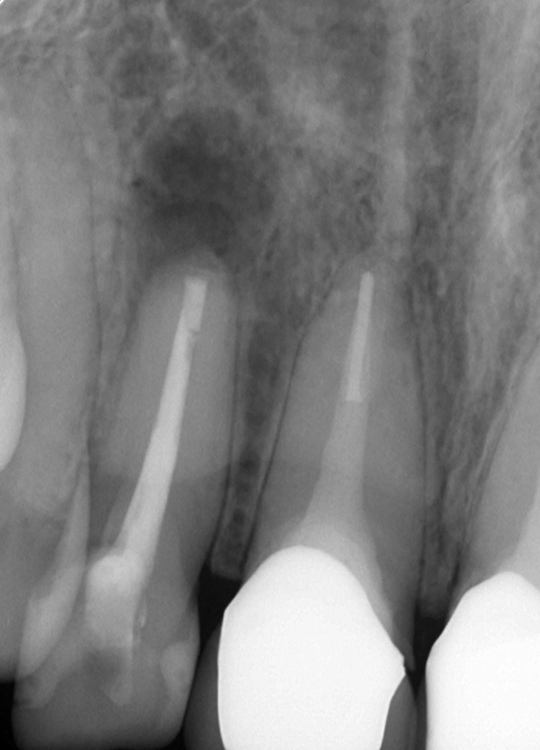

術直後レントゲン写真

治療後

症状はすべて改善、経過1年後

ウミの出口もなくなり外科的処置の跡はほとんどなく、被せ物も天然歯と見分けつきません

溶けて穴の空いた骨もすっかり回復して良好な状態です

外科的歯内療法は、通常の歯の中から行う一般的な根管治療だけでは治りが望めなかったり、それの経過が悪い場合や被せ物を外せず一般的な根の治療が行えない場合に行います。根尖病変(根の先の周囲の炎症)はバイ菌が原因であることを考えると、まずは、通常の治療で根管内を清掃充填治療してから行った方が確実です。大きな副作用はありませんが、外科的処置が特徴であり、たまに切開線が歯茎に残ることがあります。確実に処置できれば90%以上の確率で治癒します。今回の症例は期間的制約から2段構えの治療計画で行いました。